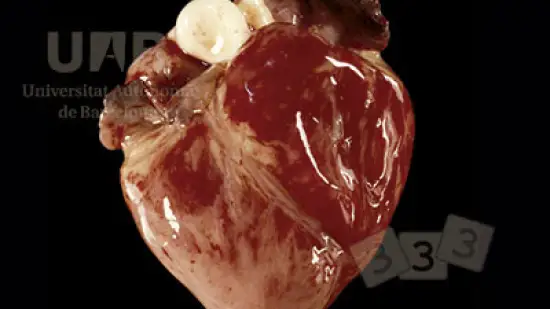

Che tipo di sostanza giallastra si deposita sull'epicardio?